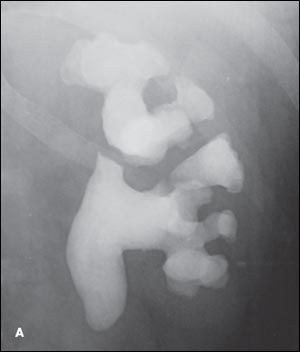

Figure 3 – A complicated staghorn stone is shown on a pretreatment radiograph (

A

) and after removal by open surgery (

B

).

Open surgery. Open surgery for renal calculi has now been supplanted by less invasive procedures.5 Studies have confirmed the advantages of endoscopic surgery (PCNL) over open surgery for staghorn stones.15,16 Open surgery is mainly reserved for patients with large, extensively branched, complex staghorn stones (Figure 3), those with altered renal anatomy, and those with coexisting renal abnormalities that require a simultaneous reconstructive open procedure. However, for a kidney with poor renal function (differential kidney function of less than 15%), simple nephrectomy might be more definitive and beneficial for the patient than multiple complicated endoscopic stone removal procedures.